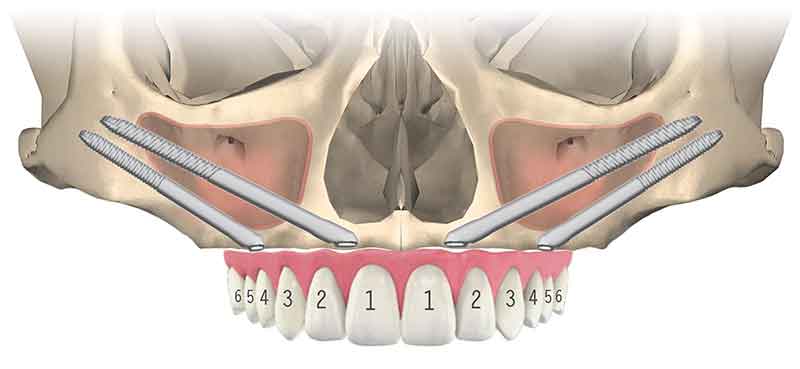

噛む力が強い場合や、上下顎の噛み合わせの関係を考慮し、前方に4本のインプラントを入れ、後方にザイゴマインプラントを用い上部構造を支える場合があります。一般的にオールオンフォーハイブリッドプラスツーと呼びます。

03All-on-4 Double Zygoma

前方、後方にザイゴマインプラントを用い上部構造を支える方法を、一般的にオールオンフォーダブルザイゴマやクアッドザイゴマと呼びます。上顎骨が大きく萎縮してしまったケースに対し、ザイゴマインプラントのみを用いる非常に難易度が高い治療法です。

人によって左右の上顎洞の形態が異なる為に、片則のみザイゴマインプラントを用いたり、骨欠損の状態によりインプラントを前方に入れる事が出来ない場合等、変則的にザイゴマインプラントを用いる事もあります。